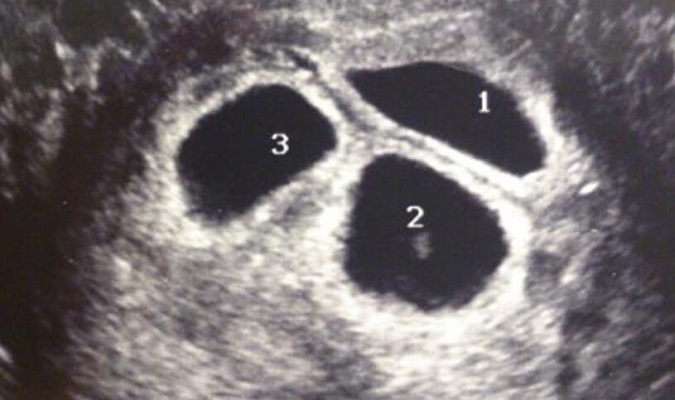

El examen de ultrasonido reveló un secreto

La pareja incansable en búsqueda de su bebé quedaron sorprendidos luego de que la tercera madre natural los eligiera. De hecho estaban tan entusiasmados que nuevamente acompañaron en cada paso a la mujer. Esta nueva madre los hizo partícipes de todo, hasta de los exámenes de ultrasonido.

En aquella jornada, Sarah y Andy verían a su niño por primera vez, pero algo extraño que develó el monitor del ultrasonido los sorprendió. Todo parecía normal para la madre natural pero al girar hacia la pantalla... todos quedaron schokeados.

Nadie esperaba ver tres bebés

Tanto Sarah y Andy como la madre natural quedaron impresionados al ver los tres latidos de corazón en el monitor del ultrasonido. Habían trabajado tan duro para conseguir su niño que habían sido bendecidos el triple.

Los Justice sabían que este era el premio que les estaba esperando al final del recorrido. Ellos no esperaban adoptar a tres niños pero una vez que se descubrió ésto, lo tomaron como una normalidad el quedarse con los tres. Excitados por el futuro que les esperaba, los Justice pidieron el proceso de adopción y se prepararon para las audiciones restantes.